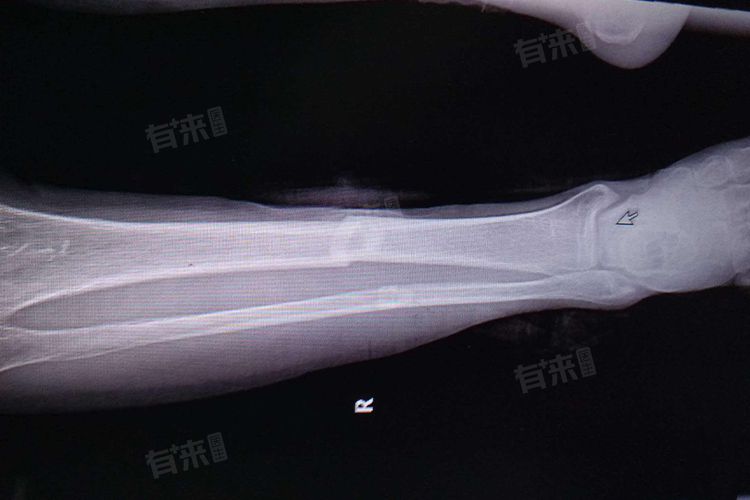

小腿骨折后腿可下垂的时间因人而异,通常轻度骨折经过妥善固定和初期治疗,2-3 周左右可尝试短时间下垂,严重骨折可能需要 4-6 周甚至更长时间,保守治疗一般 3-4 周在医生评估下可逐渐尝试,手术治疗术后 1-2 周可开始短暂下垂,完全正常下垂可能需要 4-6 周甚至更久,需综合考虑,患者应严格遵循医生建议进行康复训练。

- 严重骨折:对于严重的小腿骨折,如粉碎性骨折或伴有明显移位的骨折,恢复时间会明显延长。可能需要4-6周甚至更长时间才能考虑将腿下垂。严重骨折需要更复杂的治疗和更长时间的固定,以确保骨折部位的稳定愈合。